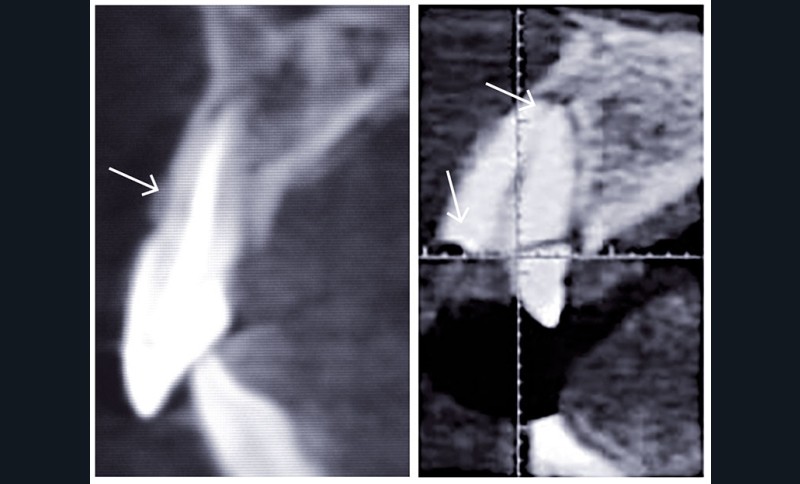

Evalués lors de l’examen clinique, ils orienteront le choix de la thérapeutique la plus appropriée à la situation clinique rencontrée. Les travaux de Braut et coll. (3) révèlent ainsi l’importance de l’épaisseur de la paroi alvéolaire vestibulaire en regard de l’édentement dans le choix thérapeutique. Il est judicieux de s’assurer rapidement de sa présence et de mesurer son épaisseur par un examen radiographique de type cone-beam (fig. 1). Trop fine, moins de 1 mm d’épaisseur, elle demandera un comblement osseux préalable, ou conjointement, à la mise en place d’un implant (4).